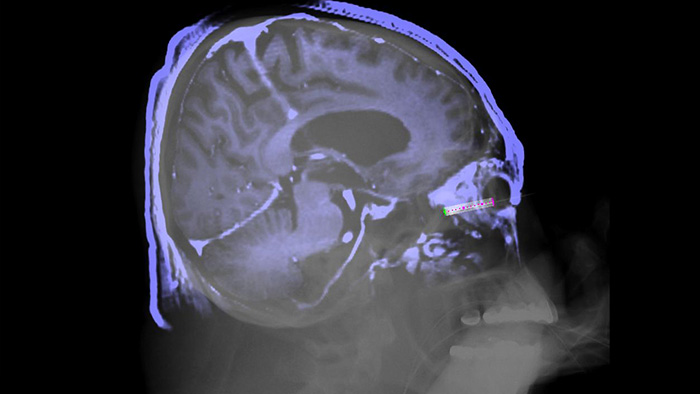

The SmartCT solution enriches our outstanding 3D interventional tools with clear guidance, designed to remove barriers to acquiring 3D images in the interventional lab. It simplifies 3D acquisition to empower all clinical users to easily perform 3D imaging, regardless of their experience1. Once acquired, 3D images are automatically displayed within seconds2 on the touch screen module in the corresponding rendering mode. On the same touch screen, the user can easily control and interact with advanced 3D visualisation and measurement tools.

This X-ray acquisition technique generates a complete high-resolution 3D visualisation of cerebral, cardiac, abdominal or peripheral vasculature from a single rotational angiography run – all controlled via the touch screen at the table. This can improve visibility of tortuous or complex anatomy that may not be seen on a 2D or DSA image.